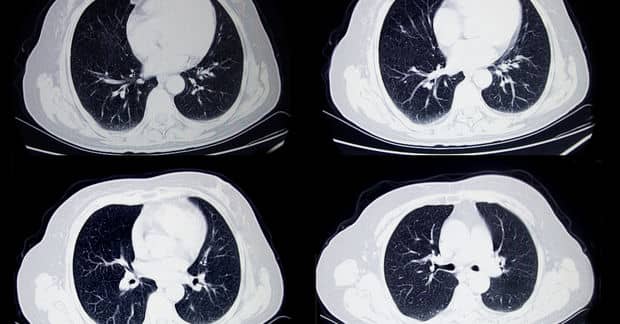

Optellum, a machine learning startup, is bringing an AI system that detects lung cancer to the masses.

The system analyzes cell clumps in scans, and Timor Kadir, the company’s chief science and technology officer, said that it could diagnose close to 4,000 patients with lung cancer per year at an earlier stage than a doctor could.